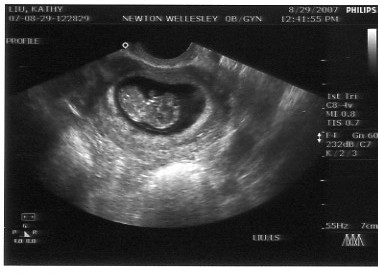

By the beginning of August, Jon was constantly bugging Kathy to take a home pregnancy test. She kept putting it off because first he was in Europe for work, then they went on a cruise to Bermuda with the Liu's, and then Jon was off to China. When Jon finally stopped traveling all over the globe, Kathy finally took the test - which was instantly positive (no need to wait the requisite 3 minutes!). After a confirmation test with Kathy's primary care physician, then there was a scamble to find an obstetrician (thanks, Anne B!) and make the first appointment. Basically, since we had no idea WHEN we got pregnant, Kathy got an appointment right away to get an ultrasound to judge how far along the baby already was. It turns out we were 9 weeks along (the fetus was about 3 cm long). When Jon saw the pictures, he began referring to the baby as his "beanie baby" since it looked like a bean to him.